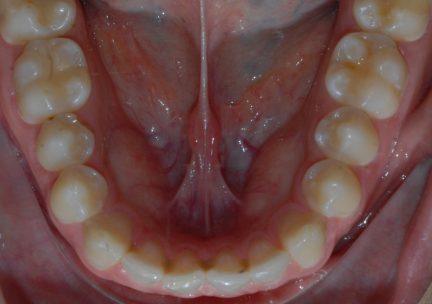

Classe I, arcades étroites, chevauchement, espacement, diastème

État initial